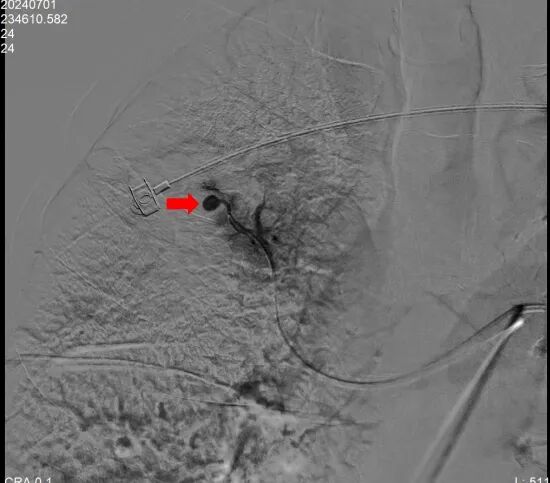

手術(shù)圖片:(紅色箭頭處為肋間動(dòng)脈造影顯示肺動(dòng)脈假性動(dòng)脈瘤)

行肺動(dòng)脈超選擇造影將微導(dǎo)管引入假性動(dòng)脈瘤供血?jiǎng)用}

使用4枚彈簧圈堵塞動(dòng)脈瘤供血?jiǎng)用}后在經(jīng)肋間動(dòng)脈造影已未見瘤體顯示,栓塞成功,然后分別予以支氣管動(dòng)脈和肋間動(dòng)脈栓塞,患者術(shù)中即刻止血。